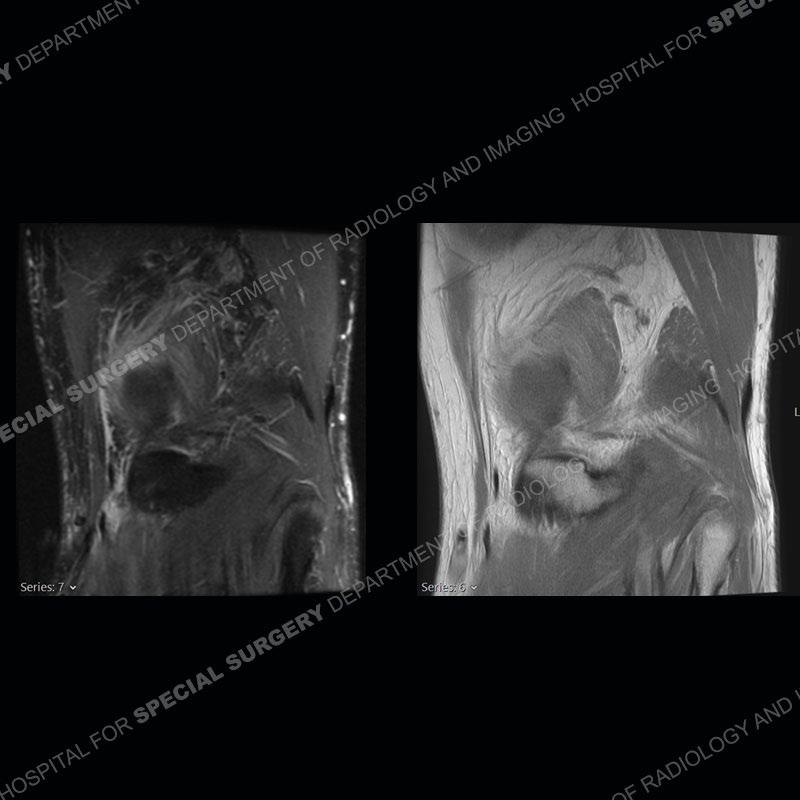

The radiographs show degenerative change of the medial compartment and a varus knee, but they are not germane to this case. No acute bony injury is present. The MRI shows edema of the posterior medial knee/soft tissue and a focal area of a partially disrupted low signal structure. The details are kept at a minimum in the findings of this case on purpose.

Fourth, use all imaging planes and different pulse sequences to make your diagnosis. The edema highlighted in this case can be seen as the obscuration of fat on the PD images but is much easier to perceive as the high signal on the IR pulse sequences. The actual disruption of the MHG myotendinous junction is only able to be seen on the axial images. On the sagittal and coronal images, we get a sense something is wrong but hard to be exact. Lastly, when you look at a study and something just seems off (as I would say the sagittal and coronal images do with that dark band of tissue posteriorly), listen to yourself and go through the study slowly and meticulously. Most of the time you will find you were right, and something indeed is present.